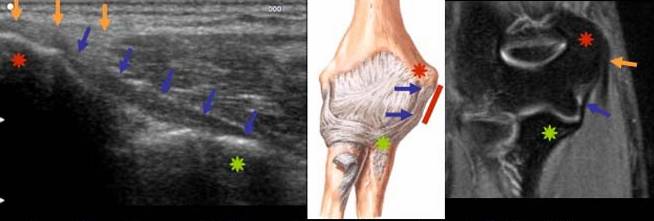

COMPRESIUNEA NERVULUI ULNAR PRIN OSTEOCONDROM SECUNDAR

Parestezii in teritoriul nervului ulnar Mica osificare →in contact cu n. Ulnar → Pe IRM mica lacuna osteocondrala a condilului →* corespunzator locului de plecare a osteocondromului